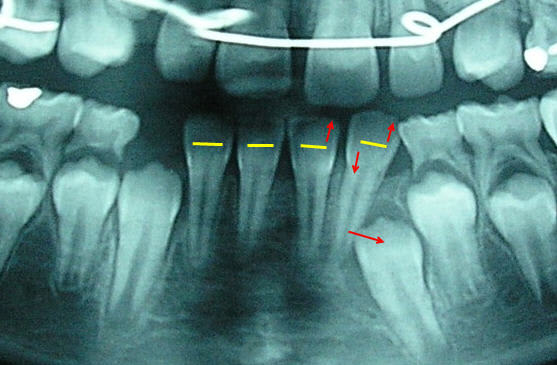

C’est la perte prématurée de 73 provoquée par l’éruption de la 32 qui a retardé l’évolution de la 33 par la suppression du « chemin » qu’elle aurait dû avoir. Regarde la quantité d’os qu’il faut encore qu’elle résorbe.